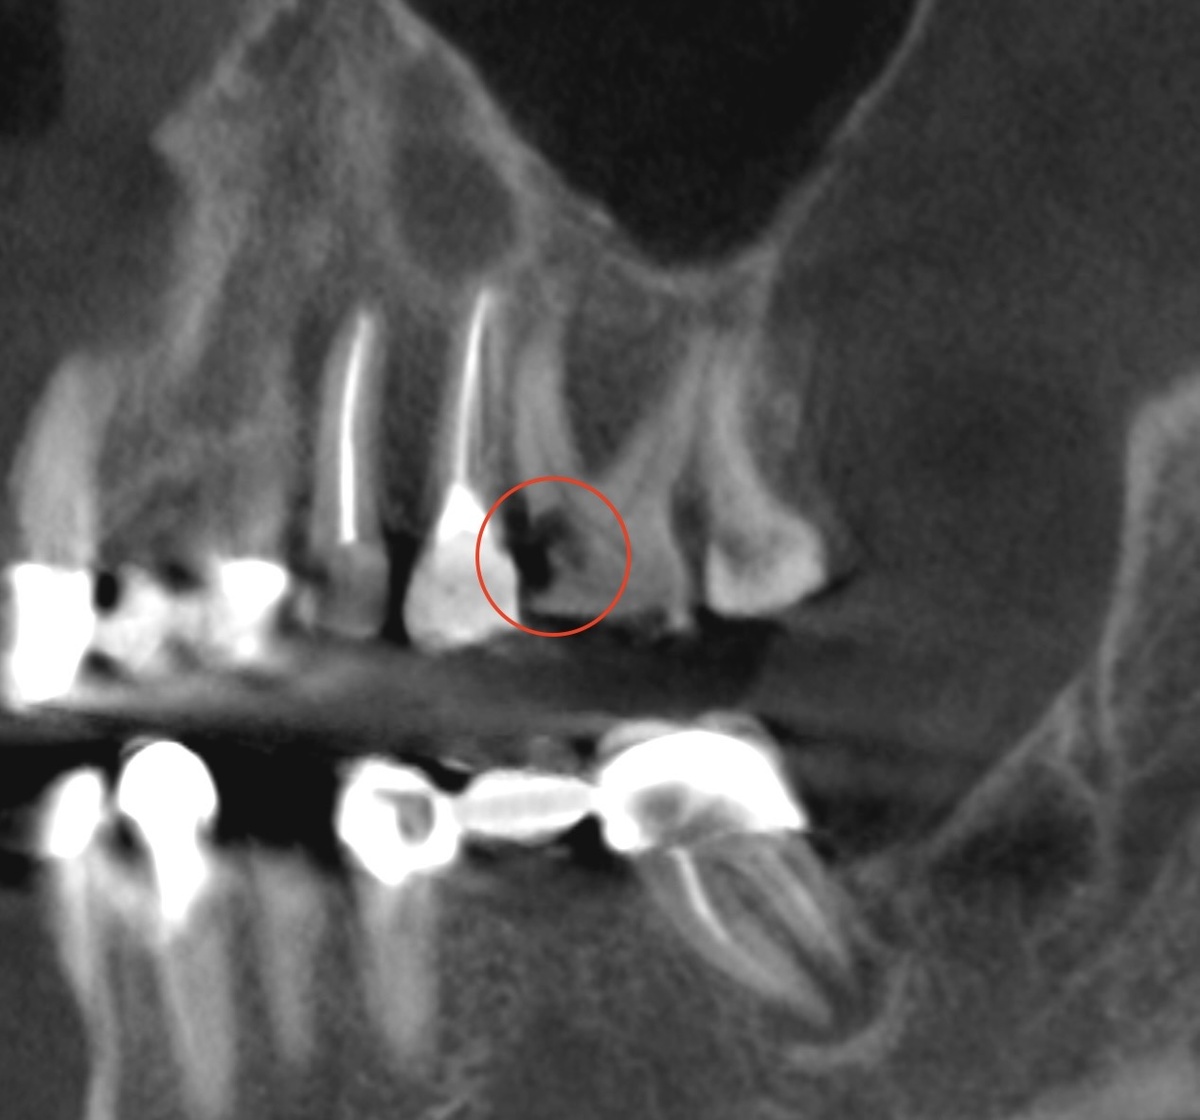

Пациентка пришла к нам на санацию перед протезированием - в жевательном отделе отсутствуют зубы, нужна подготовка. Сделали КТ, фотографии, провели осмотр.

На снимке обнаружен 26-й зуб с обширным кариозным поражением, идущим к медиально-щёчному корень - это по КТ выявили:

Кариес корня